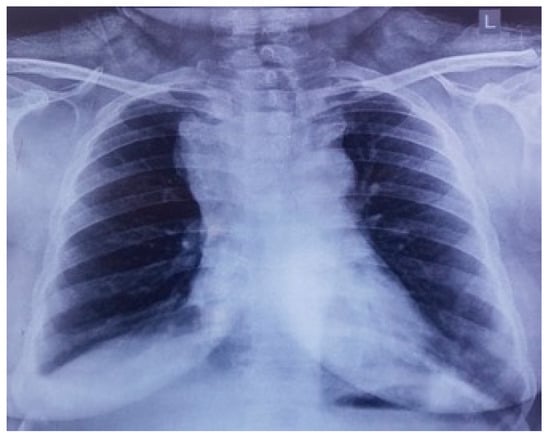

On preliminary examination, the patient was conscious with tachypnoea and tachycardia. She had puffiness with the flushing of the face, periorbital region, and neck. Oedema of both upper limbs was also noted. Jugular venous pressure was elevated, and the rest of the systemic examination was unremarkable. Preliminary blood reports were within normal limits, and a chest X-ray showed a large mass with respect to the mediastinal compartment obscuring the bilateral hila and arch of the aorta (Figure 1).

Figure 1.

Chest X-ray showing widened superior mediastinum.